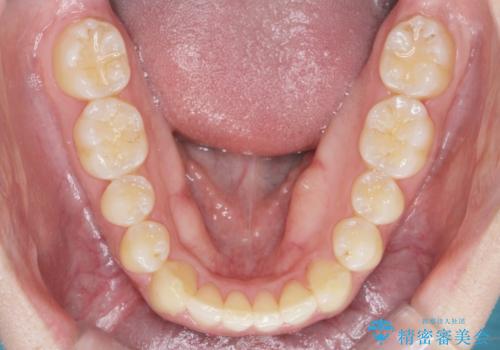

前歯が隠れていて見えない クロスバイトの矯正治療

- 「前歯が1本隠れていて見えない、歯並びを矯正治療で改善したい。」と希望され来院されました。

奥に隠れている前歯を並べられるスペースを確保したのち、歯並びを整えていきます。

前歯のスペース不足により1本だけ後方に位置している状態でしたが、しっかりとスペースを確保し配列することができました。